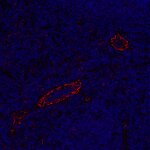

Visualization of blood vessels in a human invasive ductal breast cancer section using anti-CD31 antibody.